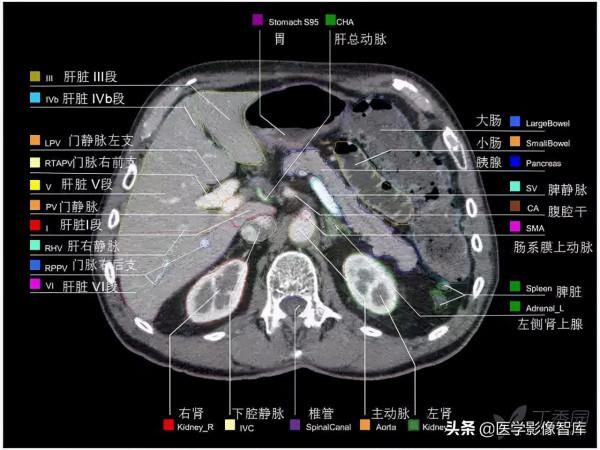

腹部CT